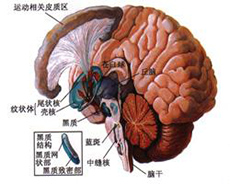

严重颅脑损伤、多发伤、复合伤

疾病介绍:严重颅脑损伤、多发伤、复合伤,多为交通、工矿事故、自然灾害、爆炸、火器伤、坠落、跌倒以及各种锐气、钝器对人体伤害。除正确诊断和及早手术外,加…【详细】